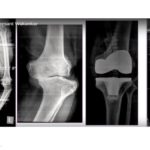

Gilula’s Arcs of the Wrist Joint

Courtesy: Harry Benjamin Laing MRCS, Ortho M8, FRCS(Tr and Orth) Tutorials